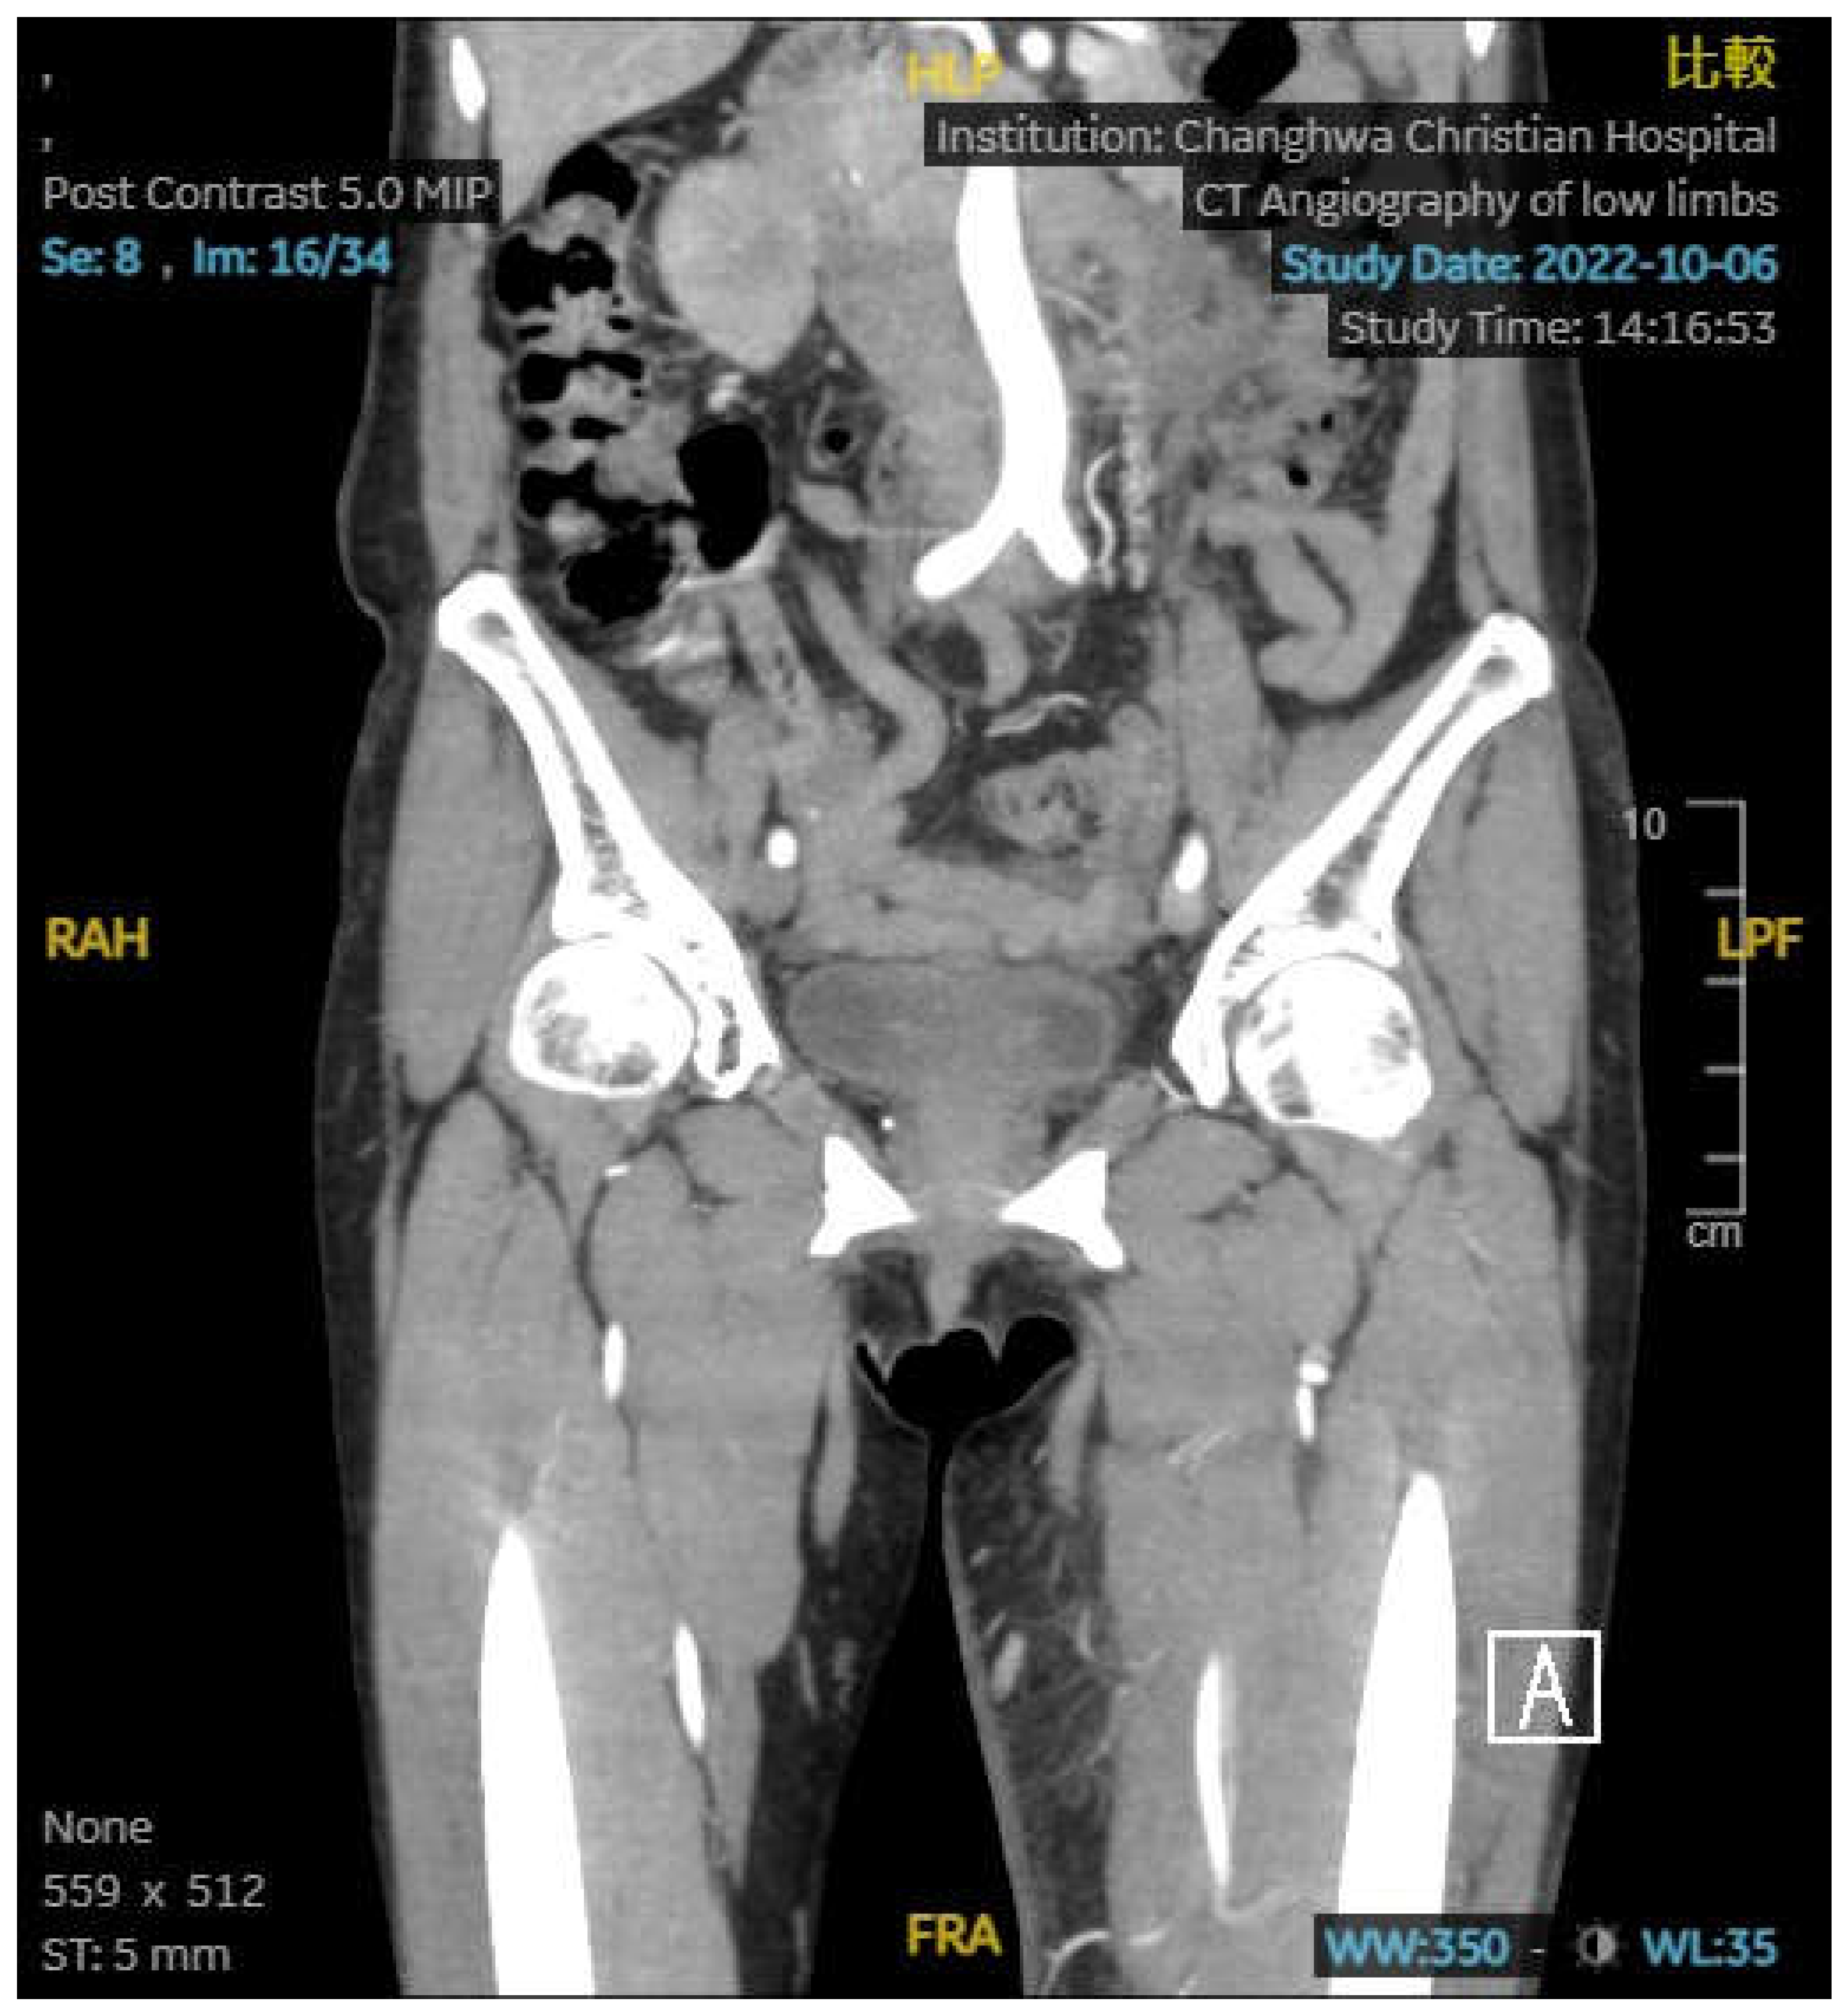

An 66-year-old female has a no medical history. She was presented with diarrhea, change in defecation habit and tenesmus and visited to outpatient department. On rectal examination, a annular mass was palpable at 5 cm from the anal verge. Biopsy from the mass showed adenocarcinoma. Pelvic magnetic resonance imaging and positron emission tomography were ordered and revealed rectal cancer, cT3N2M0. She was received neoadjuvant concurrent radiotherapy and chemotherapy followed by transanal total mesorectal excision with ileostomy. Pathology revealed pT3N2M0, stage III. She regularly visited outpatient department and ileostomy closure was applied after three months later. However, anal pain was complained. Anal nodule was found and biopsy revealed adenocarcinoma. Local recurrence was impressed and laparoscopic abdominoperineal resection was performed. We suggested infusion chemotherapy but she refused. Therefore, she was started on tablet capecitabine. After five months of operation, she complained left leg swelling. Abdominal computed tomography was ordered and it revealed May-Thurner syndrome with left side deep vein thrombosis. (Figure 1) Enoxaparin was prescribed first and rivaroxaban substituted it. Besides, stent was inserted. However, swelling persisted and lower limb computed tomography was ordered again 3 months later. It revealed May-Thurner syndrome post stenting, collapsed left proximal superficial femoral vein related to external compression, and diffuse calcification and area of low density in the left thigh muscle.(Figure 2,3) Computed tomography biopsy was applied and pathology revealed adenocarcinoma. On the other side, she had peritoneal carcinomatosis and intestinal obstruction and ileocecal bypass was performed. Target therapy with chemotherapy was given and she passed away one year later.

Figure 1. Coronal view of abdominal computed tomography revealed May-Thurner syndrome with left side deep vein thrombosis.